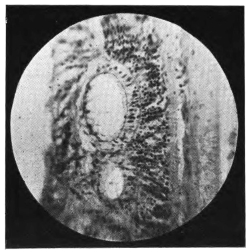

PLATE IV.

22.

LENS DISLOCATED BEHIND RETINA

curly bracket span

48

23.

FISTULA OF THE CORNEA

24.

CAPSULO-CORNEAL SYNECHIA

25.

RETINO-CORNEAL SYNECHIA

26.

SCLERAL FISTULA

27.

"    " (MAGNIFIED)